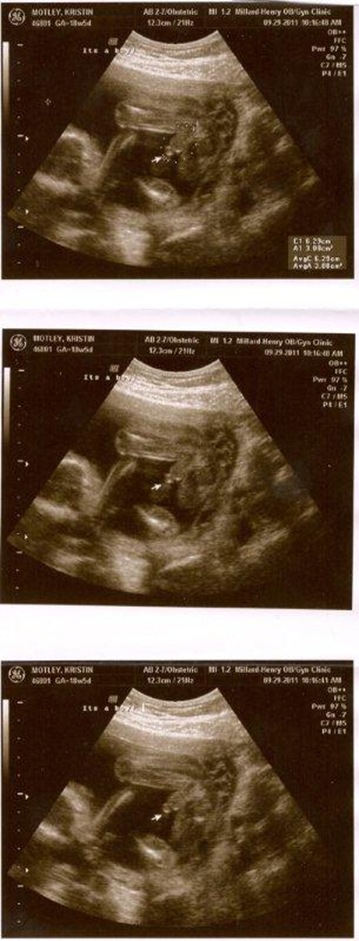

I forgot to post pictures of Baby Motley! These were taken on September 29th, last Thursday, prior to the gender reveal party. Kristin’s doctor told her the baby was measuring perfectly and everything looked great. And her due date remains the same, on February 25th.

Look at that little foot! Such a precious miracle!

And then there was no doubt that we are having a boy!